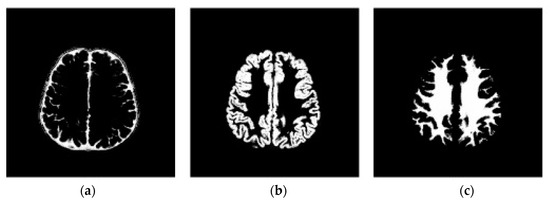

3.1. Step 1 Preprocessing Phase